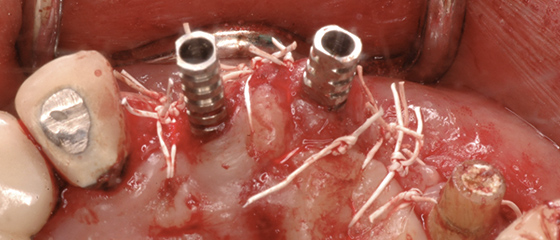

手術の詳細

上顎前歯部を再インプラント

治療は終了し経過観察の時点で、上の前歯部のインプラントを繋げたブリッジが動揺しており、インプラントが抜けてきました。

インプラントを撤去した穴からは膿が出てきました。撤去したインプラント表面には骨はついておらず、プラークがべったり付着していました。

撤去したインプラントの隣にあるブローネマルクインプラントは、既に周囲の骨が溶けて無くなっており、ネジが露出していたため、その部分をしっかりと清掃し、骨補填材を入れました。また、抜けたインプラント部分には、2本のブローネマルクインプラントを埋入し、縫合したのち、仮歯を固定しました。